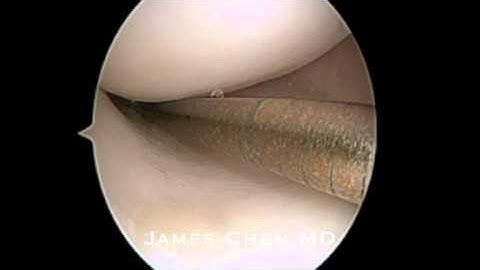

Meniscus Bucket Handle Tear